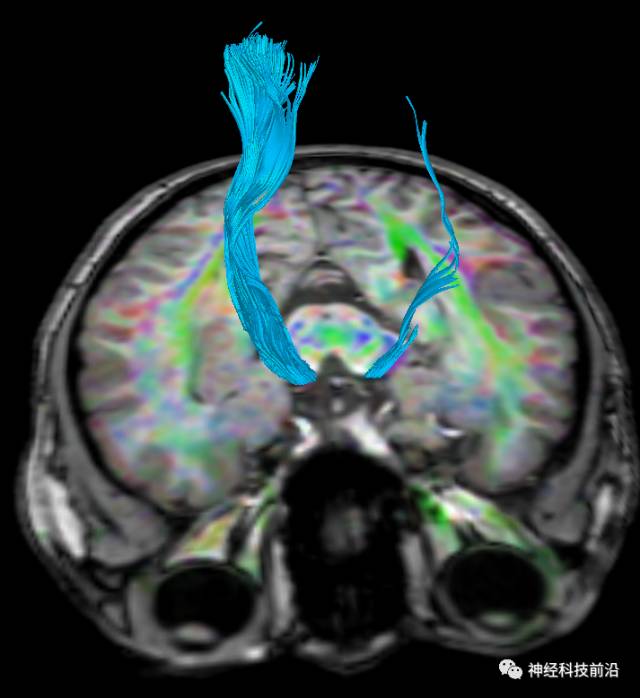

DTI原始图像与T1融合图像

上述纤维束与小脑中脚的位置毗邻

终上所述:脑干高信号为一近环形纤维束,内囊后肢高信号为皮质脑桥束,皮质脊髓束在中脑位置略靠后。高信号位于中脑前缘,是皮质脑桥束的位置所在,另外有部分桥连纤维。